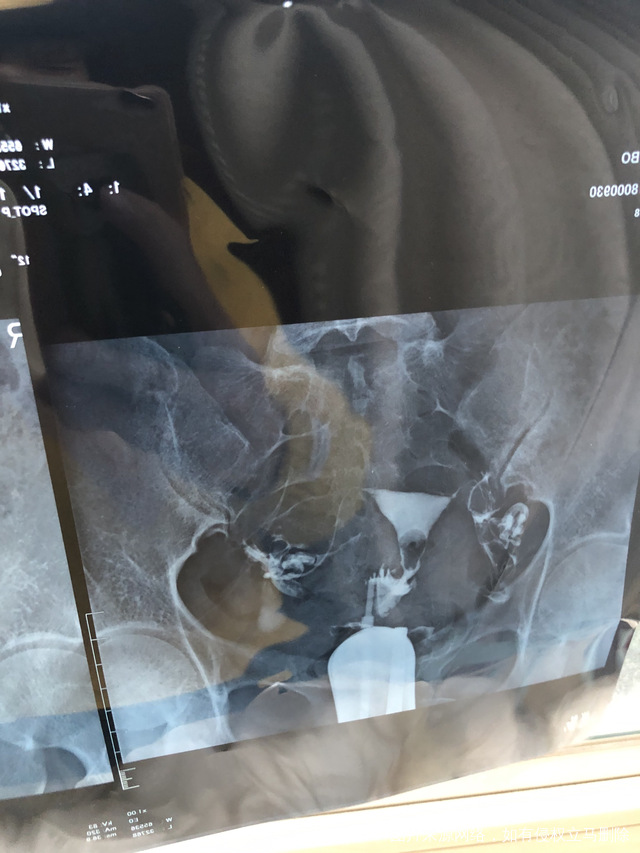

一直没有怀孕检查输卵管通而极不畅我这种情况是

一直没有怀孕,检查输卵管通而极不畅,我这种情况是要怎么治疗比较好?